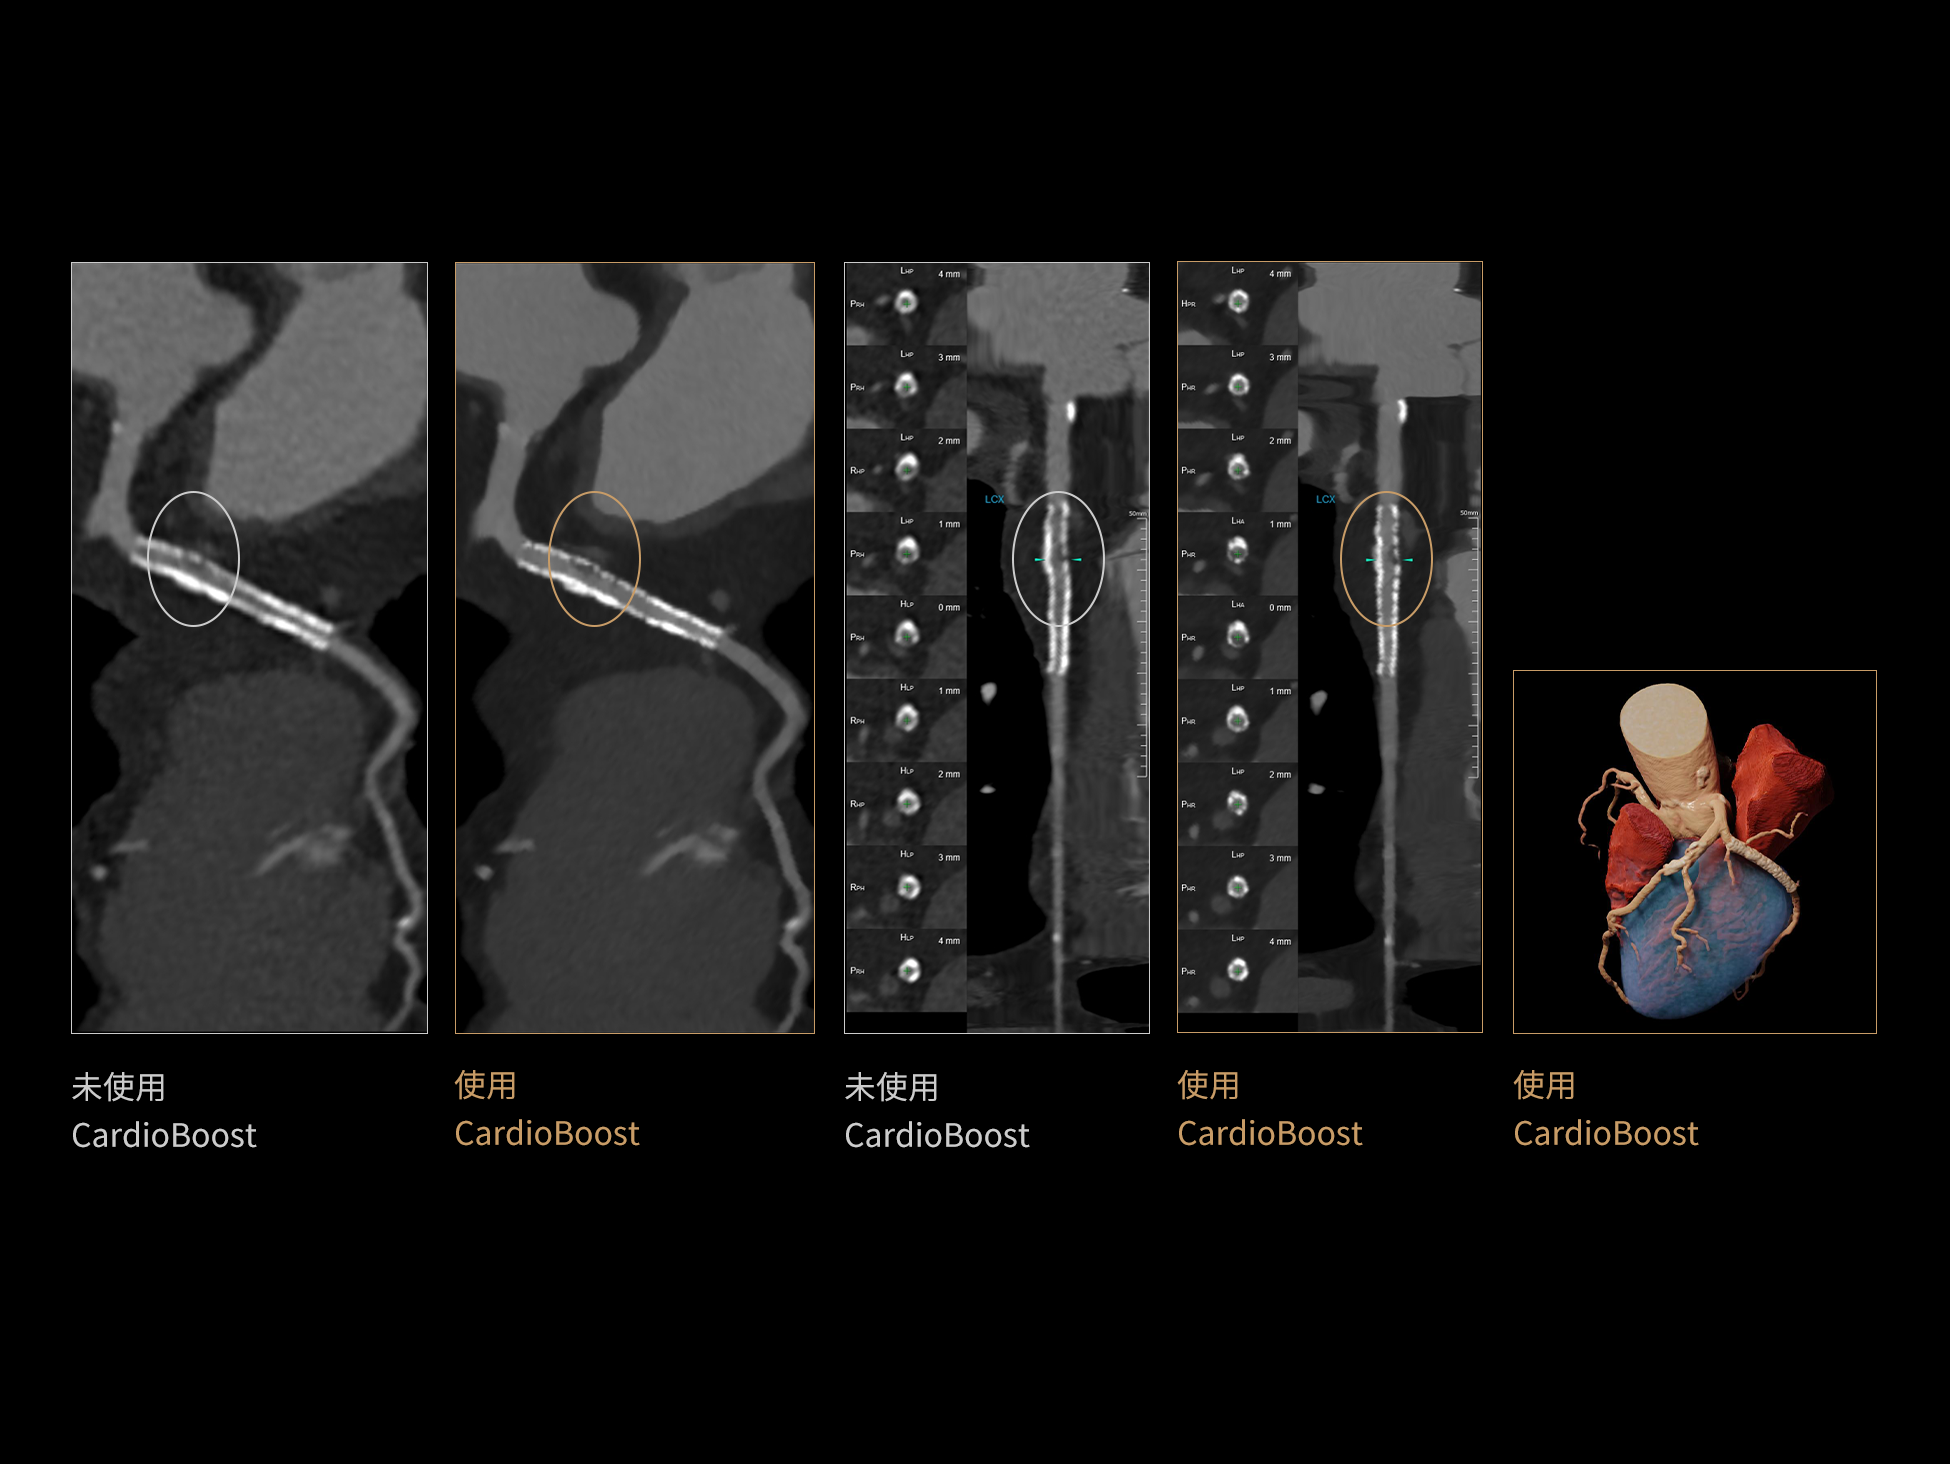

CardioBoost:专属网络设计,重塑心脏影像表现

目前心脏的 CT 检查还存在辐射剂量偏高、空间分辨率不足、 致密钙化伪影影响冠脉狭窄程度评估等方面的限 制[1][2]。CardioBoost 技术专为心脏 CT 高清成像而开发,通过 3D 神经网络的深度学习技术,利用先进的注意力机制在识别关键成像特征方面的出色表现,能够精确地聚焦于斑块、支架以及微小血管等关键细节,清晰展示这些结构与冠脉血管的边界,从而显著提高诊断的准确性,并提升医生的诊断信心。创新的 CardioBoost 心脏图像重建算法,不仅实现了图像清晰度的提升和伪影的去除,更能在减少辐射剂量的同时,保证心脏图像的高质量和图像纹理的自然。

采用 3D 神经网络的空间结构优势与精细的组织分类能力,CardioBoost 技术优化了组织对比,高清展示血管斑块,使斑块与血管边缘的轮廓清晰可辨,提升斑块诊断与评估的精确性。

借助 3D 神经网络设计、空间注意力机制聚焦与特征强化作用,CardioBoost技术提升图像的空间分辨率,实现冠脉支架的高清成像,对支架形态与管腔通畅度的评估更精准。

CardioBoost 整合先进的 3D 神经网络和空间注意力机制,大幅增强数据处理的速度与精确度。该技术能有效抑制由致密钙化引起的晕状伪影,清晰展现钙化斑块的原始结构和大小,对冠脉狭窄的评估更加精确可靠。

对比度强化模块

分辨率强化模块

伪影抑制模块